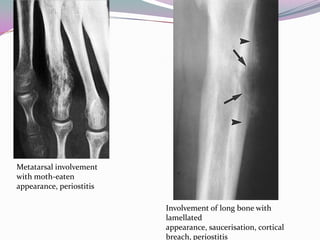

Metatarsal involvement

with moth-eaten

appearance, periostitis

Involvement of long bone with

lamellated

appearance, saucerisation, cortical

breach, periostitis

Metatarsal involvement with moth-eaten appearance,periostitis Involvement of long bone with lamellated appearance, saucerisation, cortical breach, periostitis